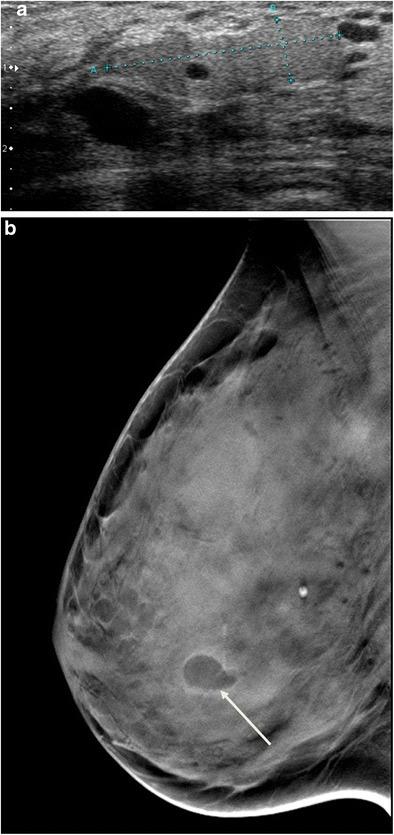

Hyperechogenicity is a sign classically reported to be in favour of a benign lesion and can be observed in many types of benign breast lesions such as hamartoma, lipoma, angiolipoma, haemangioma, haematoma, fat necrosis, fibrosis and galactocele, among others. However, some rare malignant breast lesions can also present a hyperechoic appearance. Most of these hyperechoic malignant lesions present other characteristics that are more typically suggestive of malignancy such as posterior shadowing, a more vertical axis or irregular margins that help to guide the diagnosis. Post magnetic resonance imaging, second-look ultrasound may visualise hyperechoic malignant lesions that would not have been identified at first sight and radiologists must know how to recognise these lesions.

• Some rare malignant breast lesions can present a hyperechoic appearance. • Malignant lesions present other characteristics that are suggestive of malignancy. • An echogenic mass with fat density on mammography does not require biopsy.

高回声是一种传统上被认为提示良性病变的征象,可在多种类型的乳腺良性病变中观察到,如错构瘤、脂肪瘤、血管脂肪瘤、血管瘤、血肿、脂肪坏死、纤维化和积乳囊肿等。然而,一些罕见的乳腺恶性病变也可呈现高回声表现。这些高回声恶性病变大多还具有其他更典型的提示恶性的特征,如后方声影、更垂直的长轴或不规则边缘,有助于指导诊断。磁共振成像后,二次超声检查可能会发现初次检查未发现的高回声恶性病变,放射科医生必须知道如何识别这些病变。

• 一些罕见的乳腺恶性病变可呈现高回声表现。• 恶性病变具有其他提示恶性的特征。• 乳腺钼靶显示脂肪密度的高回声肿块无需活检。